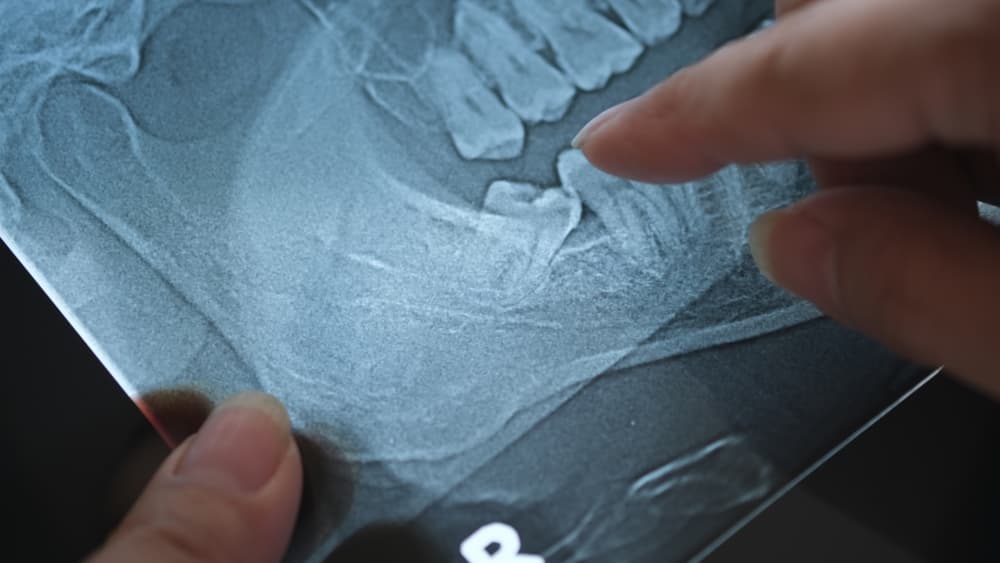

If you’re experiencing any of the above symptoms, it’s essential to consult a trusted dental provider. At Family Dental Clinic West End, we offer comprehensive assessments to determine whether wisdom teeth removal is necessary. Our experienced dental team uses advanced imaging technology to evaluate your teeth and plan the safest and most comfortable procedure for you.

The Process of Wisdom Teeth Removal in Brisbane

When you decide to proceed with wisdom teeth removal in Brisbane at Family Dental Clinic West End, you can expect a clear explanation of the procedure and what to anticipate during recovery. The removal process typically involves local anaesthesia to ensure you remain comfortable throughout. For more complex cases, sedation options may be available.